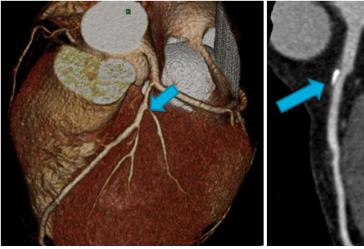

¡ã°ü»óµ¿¸Æ ÇùÂø (ÁÂ) ¹× °ü»óµ¿¸Æ ¼®È¸È­ (¿ì) ¼Ò°ß